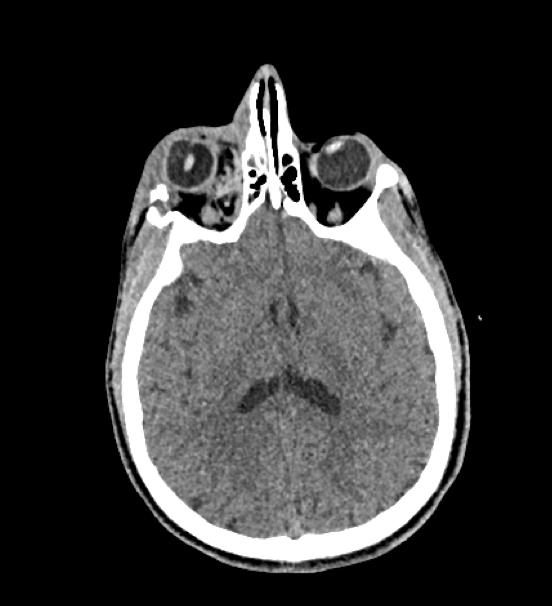

De garde, vous êtes appelé en salle de surveillance post-interventionnelle (SSPI) dans votre hôpital où vient d'être admis un patient conduit sur place par le service d'aide médicale d'urgence (Samu). Il s’agit d’un jeune homme de 20 ans, Monsieur D. Il aurait été victime, entre autres, d’un tir de Flash-Ball lors d’une rixe. Le projectile l’a atteint au niveau de la pommette et de l’orbite droites. Il présente une plaie de la région jugale haute, un œdème des paupières supérieure et inférieure. Vous ne visualisez pas le globe oculaire spontanément. Il est hémodynamiquement stable.

Traumatisme orbitaire = à risque de fracture des parois de l’orbite et donc d’incarcération d’un muscle oculomoteur.